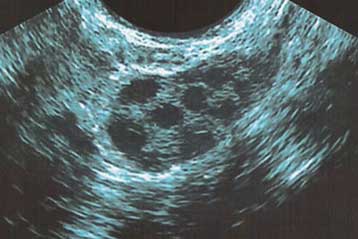

Πρώτη γέννηση από ολόκληρη μεταμοσχευμένη ωοθήκη

Ολόκληρη μεταμοσχευμένη ωοθήκη οδήγησε για πρώτη φορά στη γέννηση υγιούς βρέφους, ανακοίνωσε την Πέμπτη ομάδα Αμερικανών γιατρών, σε μια εξέλιξη ιδιαίτερα ελπιδοφόρα για τις γυναίκες που μένουν στείρες λόγω του καρκίνου.